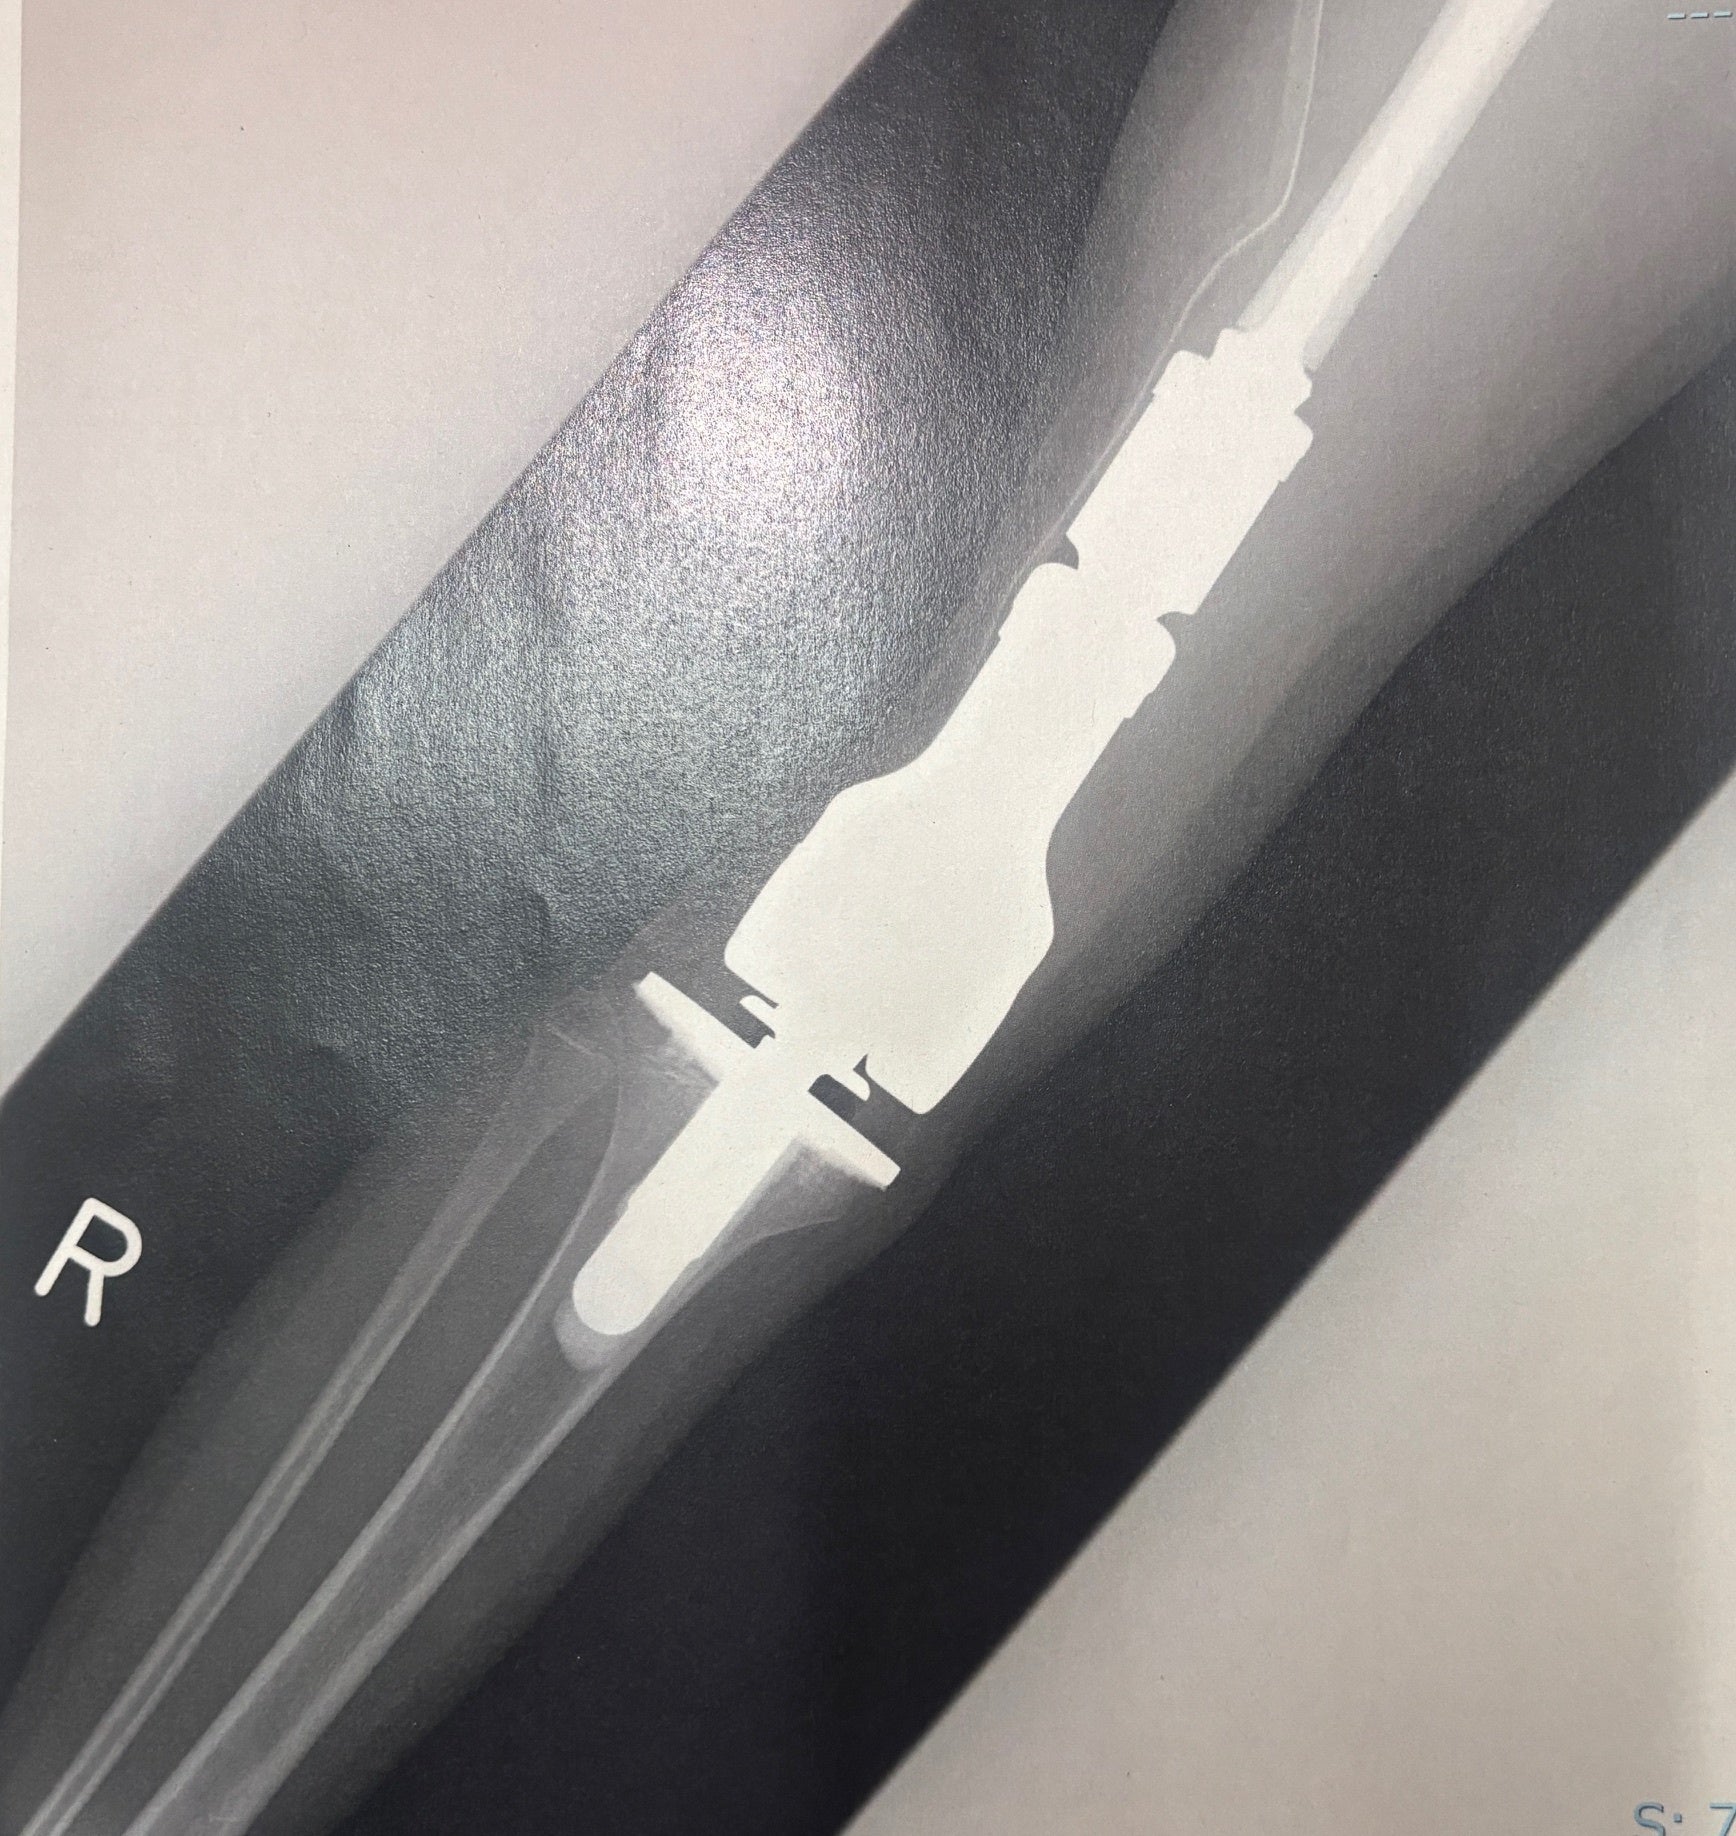

実際のレントゲン写真

実際の手術後の人工関節のレントゲン